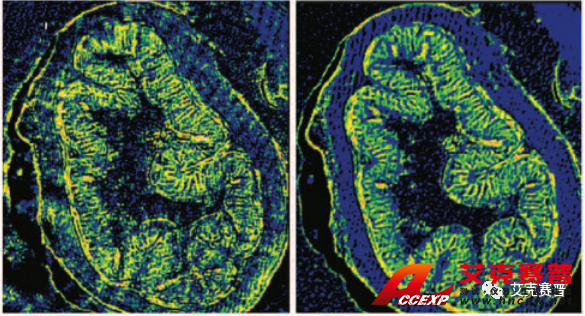

圖2顯示了布魯克已獲得專利的空間相干性抑制技術(shù)在采集激光紅外圖像時起到的改善作用。在左側(cè)的圖a和圖c中,可以看到激光束的干涉條紋對成像結(jié)果的影響。圖像看起來很模糊,有條紋和斑點。右側(cè)的圖b和圖d中相干性抑制技術(shù)在光源處消除了空間相干現(xiàn)象,從而采集到無比清晰的圖像(未經(jīng)任何后期處理)。

圖2:布魯克的空間相干性抑制專利技術(shù)改善了使用QCL成像技術(shù)采集的紅外成像的質(zhì)量: 我們得到了(d)原本的紅外成像圖,而不是(c)中干擾的傷偽影、條紋和斑點I2,該成像未經(jīng)任何后期處理。